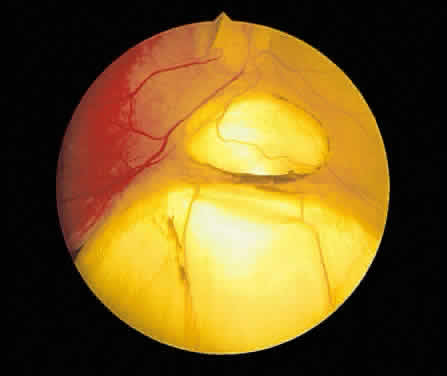

Consider the variation in pigmentation and choroidal blood flow. In one extreme, the albino, the fundus has a bright orange color because the pigment epithelium contributes little to fundus color in this condition. At the opposite extreme is the patient with congenital melanosis oculi such as seen with nevus of Ota. In this condition, the density of normal choroidal melanocytes masks much of the orange color of the choroid and changes the general fundus color to a gray-orange. If the choroid and pigment epithelium were absent focally, the observer would be looking through transparent retinal tissue at the sclera, which is white. This is the basis for the ophthalmoscopic appearance of a coloboma (Fig. 1). With the exception of the macula, in which xanthophyll pigment may impart a yellow color, the normal neurosensory retina is transparent. Despite this transparency, when the retina is focally absent, the orange color of the underlying choroid is enhanced. This color contrast may aid the ophthalmoscopic detection of retinal breaks (Fig. 2). Nevertheless, remember that the normal retina does not contribute color to the fundus. In fact, a loss of retinal transparency or the acquisition of color by neurosensory retinal tissue is indicative of a pathologic change.

Fig. 1. Fundus photograph of coloboma. The retinal pigment epithelium and choroid are focally absent. The retinal vessels are visible, although the retina is transparent.

Fig. 2. Fundus photograph of a retinal tear. The pigment epithelium and choroid visible through the retinal break have an orange-red color. The retina surrounding the tear has lost its transparency because of edema and underlying fluid.